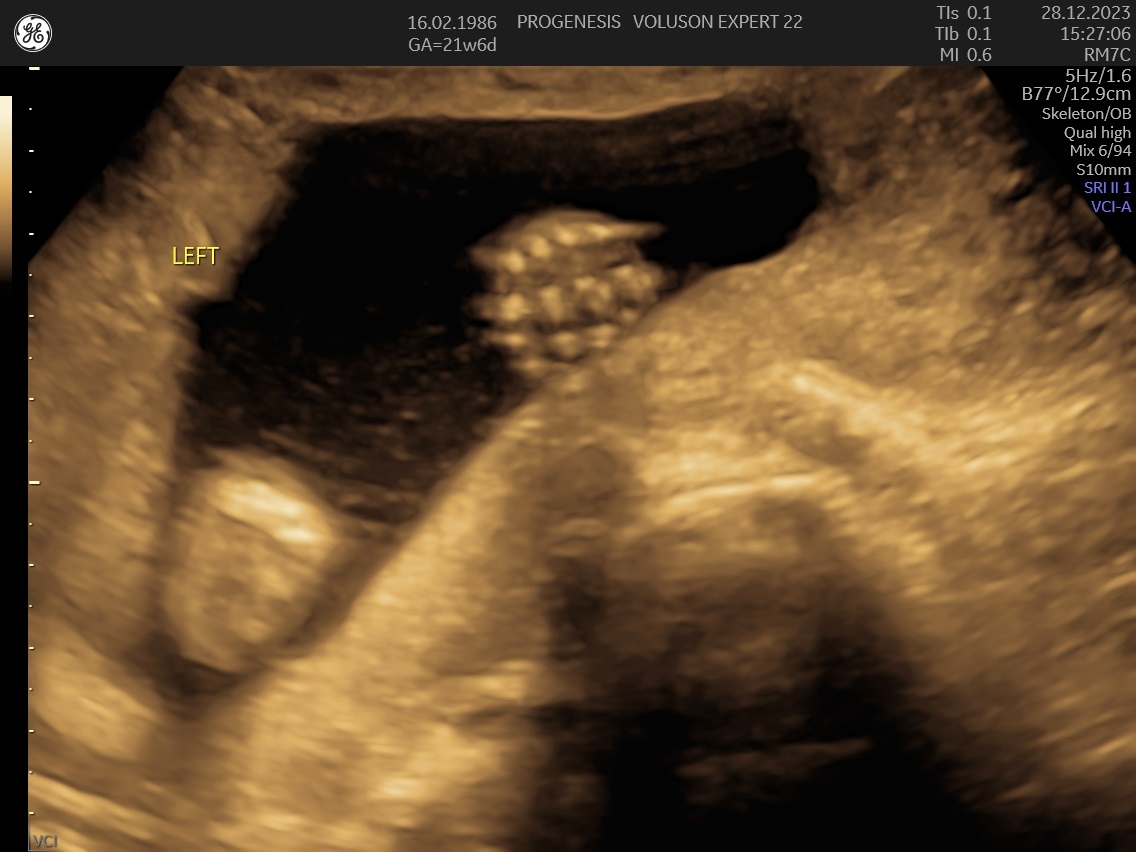

α) Η λεπτομερής αξιολόγηση της εμβρυϊκής ανατομίας, όπου αναγνωρίζονται τυχόν ανατομικές ανωμαλίες.